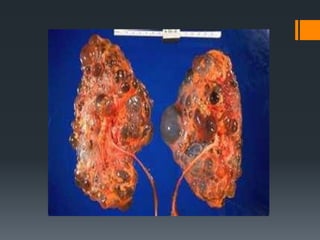

Polycystic Kidney Disease : Cluster of cysts

developing in the kidneys

Polycystic Kidney Disease: Cluster of cysts developing in the kidneys